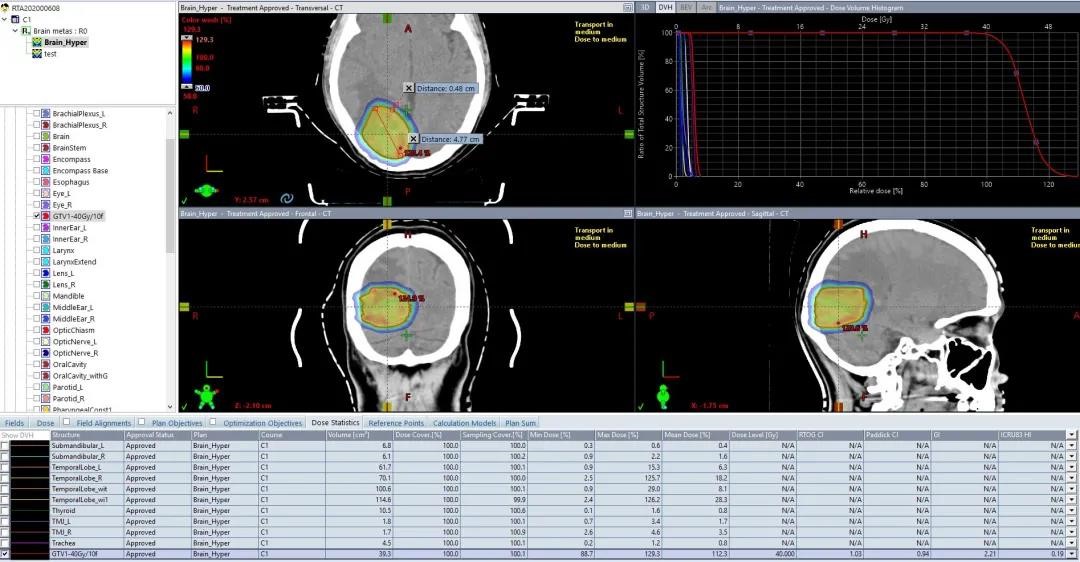

04 小脑大靶区+大脑7个小靶点

小脑:30Gy/10F,要求剂量均匀

大脑靶点:40Gy/10F,SRS照射

同时满足大脑小靶点SRS照射和小脑均匀照射